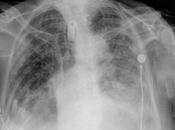

Existe proceso neumónico a nivel de pulmón derecho en lóbulo superior, con...

PA Y LATERAL DE TORAX LA PROYECCION RADIOLOGICA OBTENIDA NOS MUESTRA LOS SIGUIENTES HALLAZGOS: -Tejidos blandos, con densidad conservada, simétricos, sin... Leer el resto